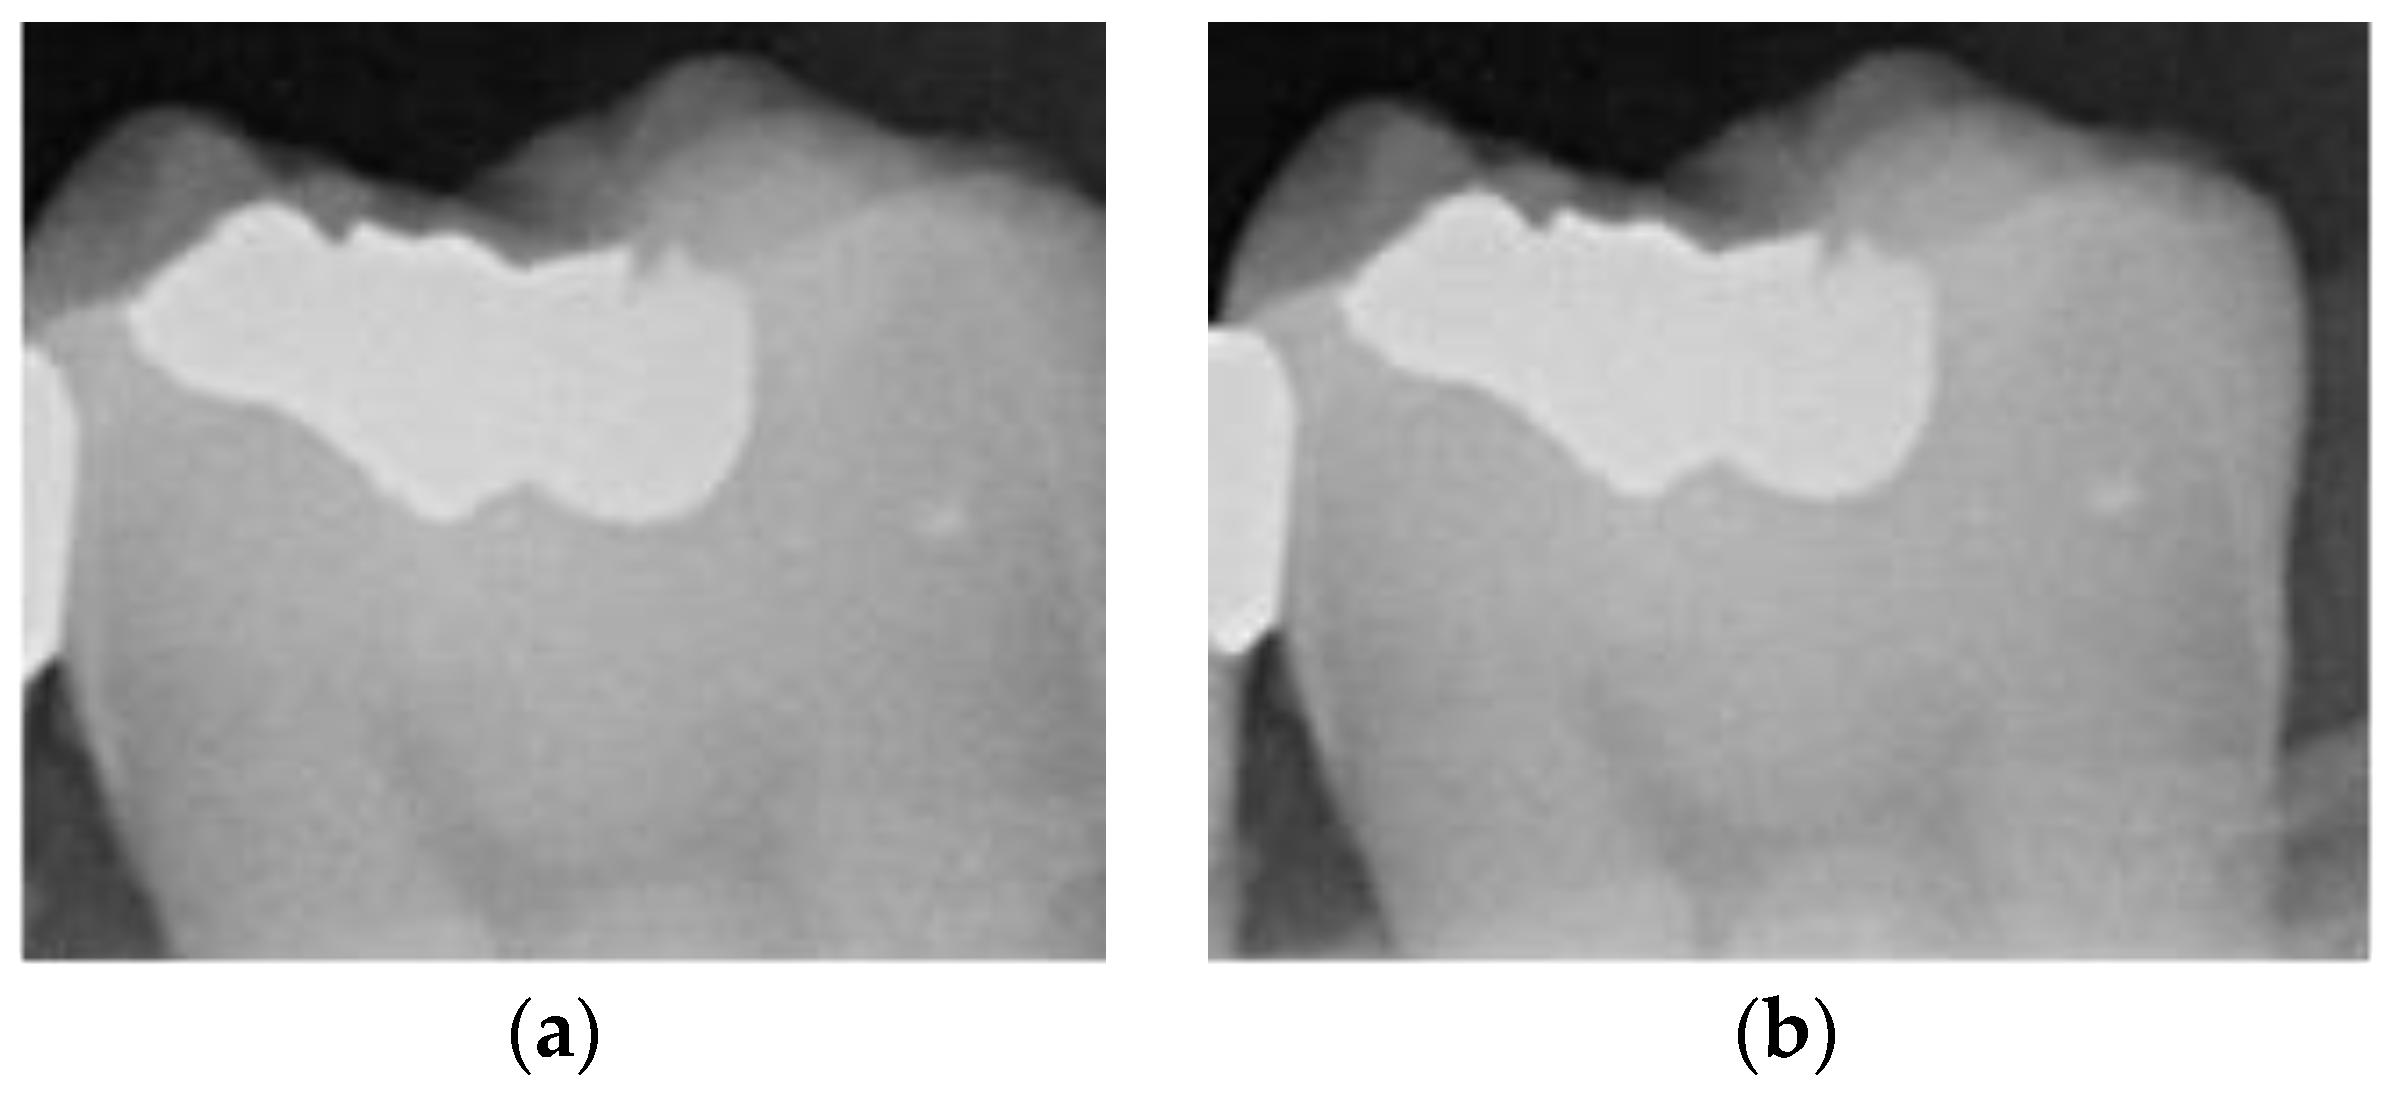

Figure 8.

Image-enhancement results: (a) binarization; (b) mathematical morphology; (c) added green line represents canny; (d) overlap onto the original image.

2.3.5. Canny Edge Detection

Since filtered and binarized images alone cannot enhance the features of dental calculus, this approach does not effectively improve the accuracy of machine learning. Therefore, this study employed edge detection to identify the contours of tooth edges, enhancing the regions of interest and thereby improving the accuracy of machine learning. The canny edge-detection algorithm applies non-maximum suppression to each pixel, retaining pixels with local maximum gradient values, which can produce continuous and accurate edges while demonstrating good resistance to noise. The edge-detection results are represented in green, as shown in Figure 8c. Finally, these results are overlaid back onto the original image, as illustrated in Figure 8d.